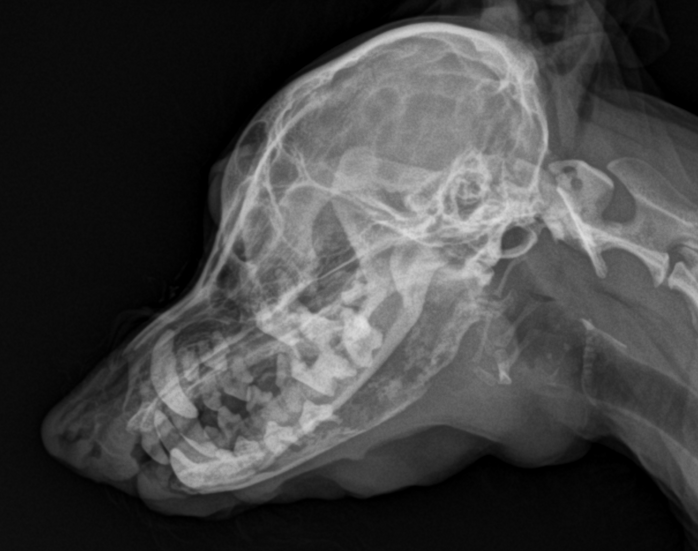

oral plasmacytoma in dog